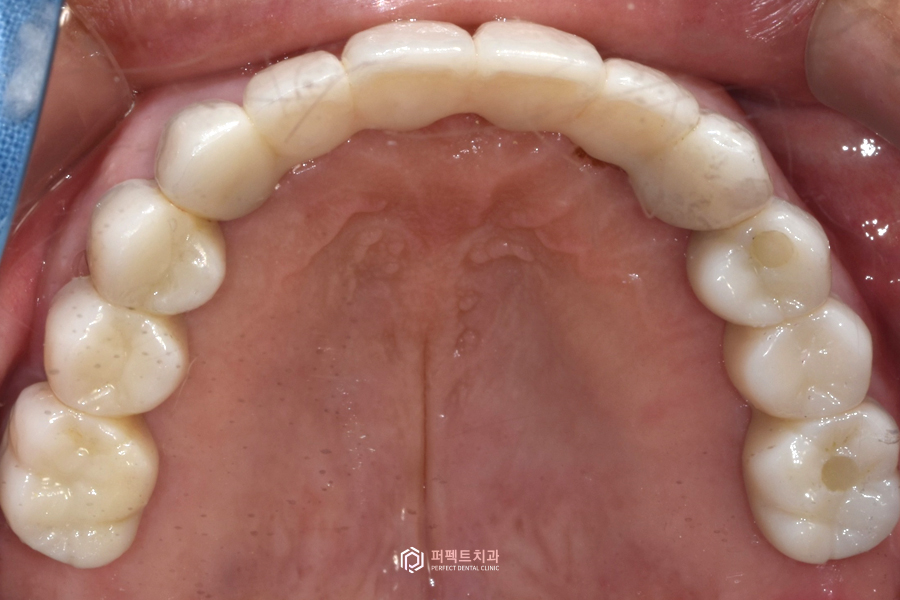

치료 후 구강사진

구강사진을 보시면 지르코니아 라는 재료를 이용해 전체를 수복했고, 교합도 깨끗하게 잘 물리도록 완성이 되었습니다.

치료 후(상악) 22.02.08~22.07.07

전 후 사진을 보시면 무너진 교합과 썩고 부러진 치아들을 수복한 케이스인 것을 보실 수 있습니다.